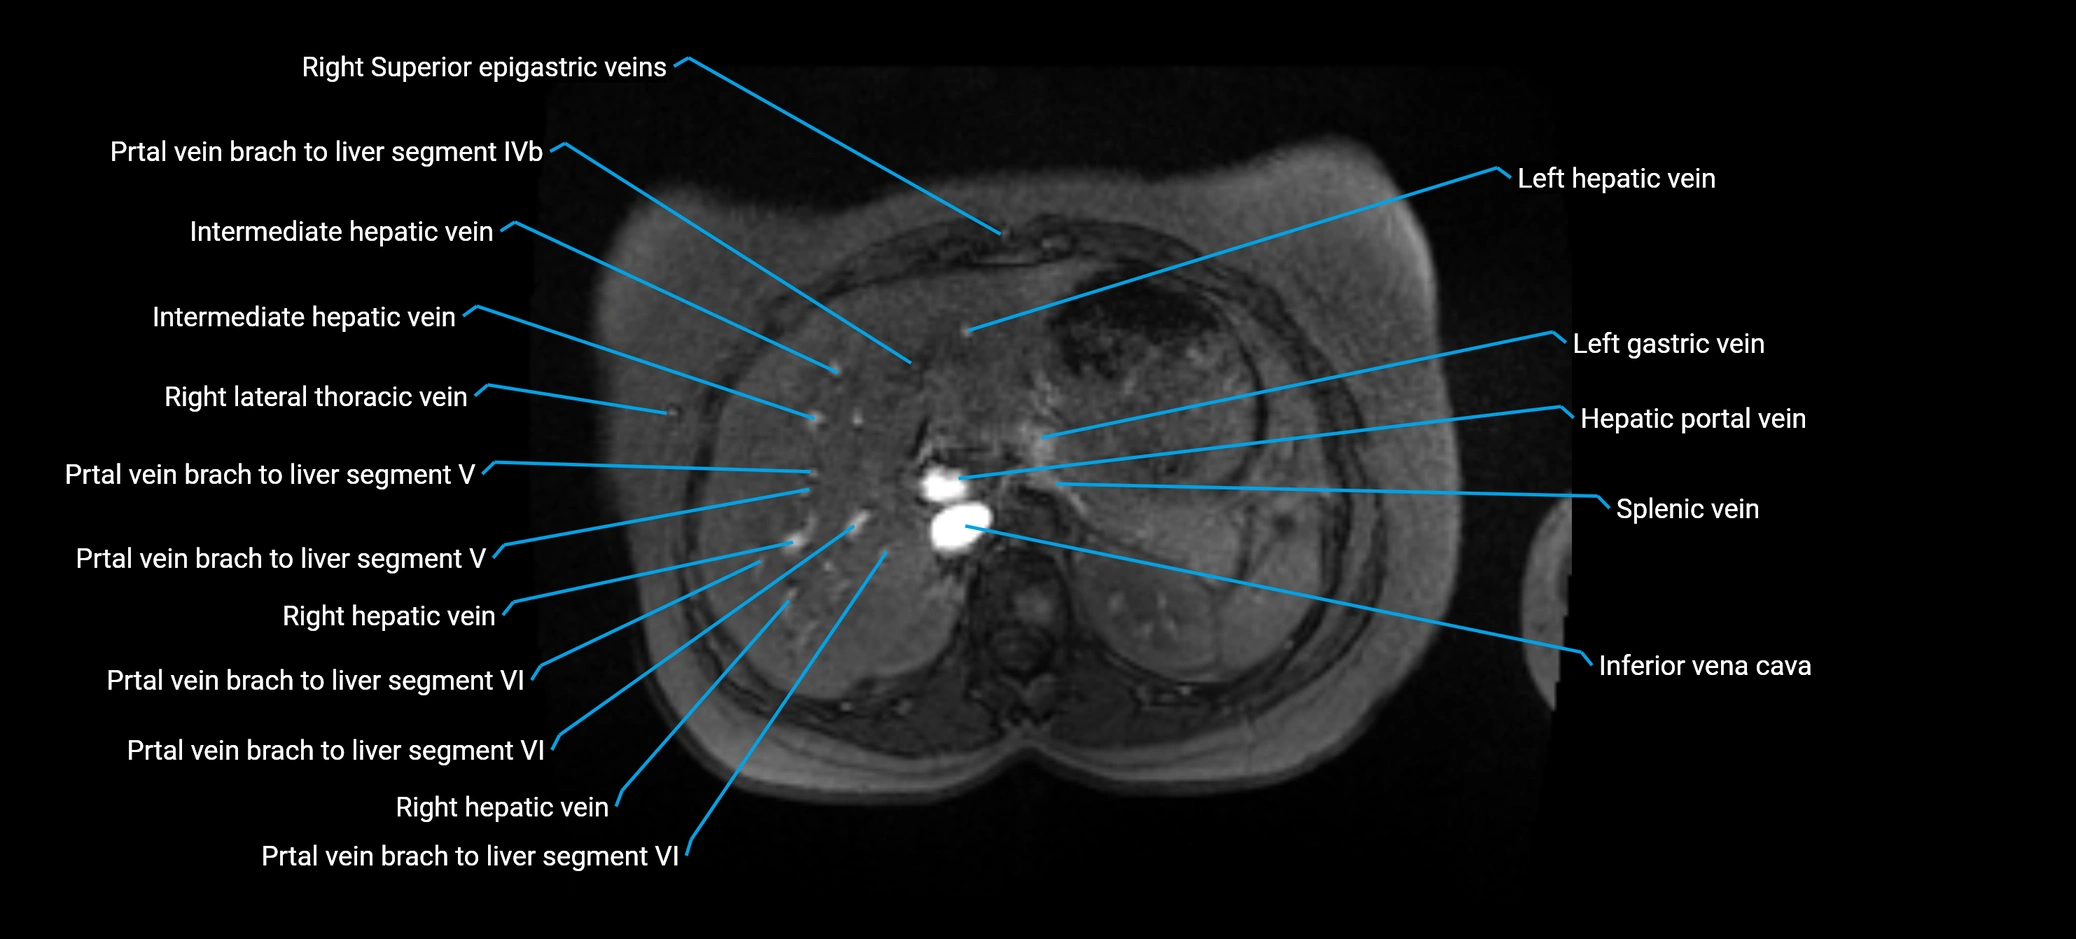

MRV TOF (Time-of-Flight MR Venography):

• Appears as a bright, high-signal vascular channel representing flowing blood

• Clearly shows branching pattern of right portal vein into anterior and posterior branches

• Best in coronal or axial reconstructions for segmental mapping

• No need for contrast, relies on flow-related enhancement

• Clearly delineates branching into segments V and VIII

• Best sequence for evaluating patency, caliber, and anatomic variants

MRI image

image